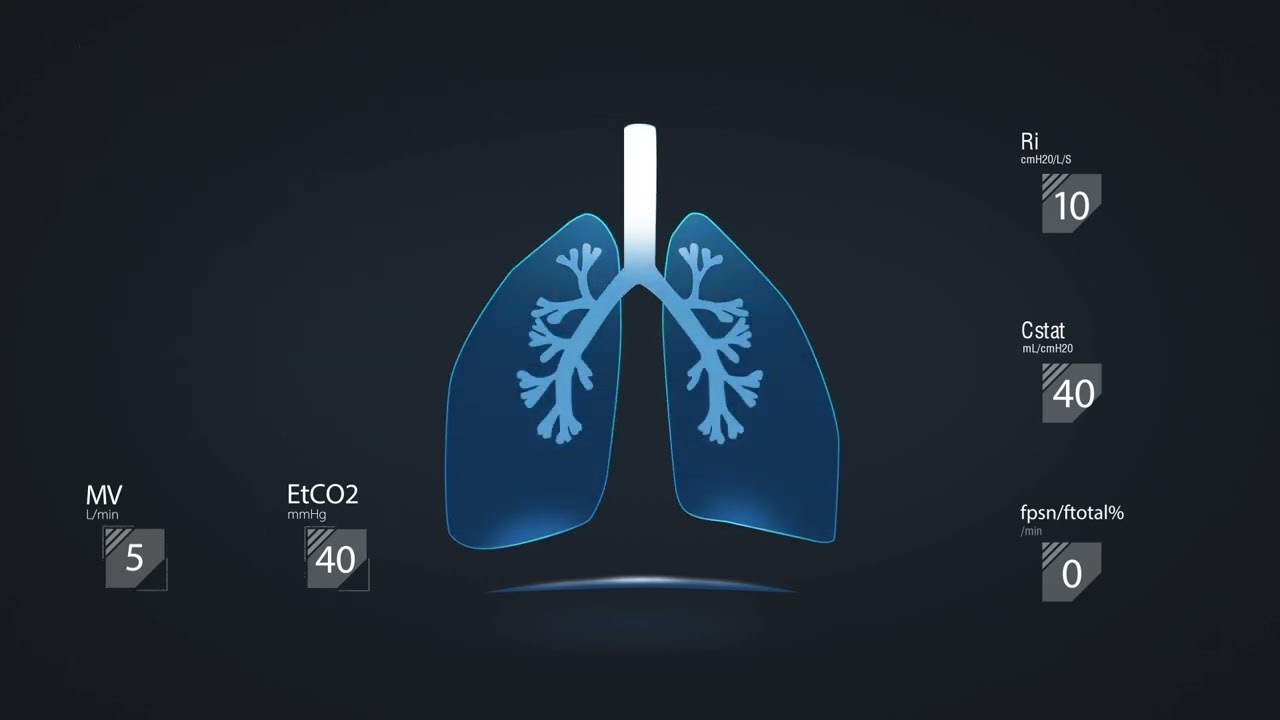

Mindray offers the most comprehensive portfolio of Point of Care ultrasound solutions that are easy to use, elevate your practice, and empower you to provide an even higher standard of care in a timely manner. From entry-level, touch-enabled systems to sophisticated, laptop or cart-based designs, our Point of Care ultrasound machines are an excellent choice to meet the demands of fast-paced environments such as Emergency Medicine, Critical Care, Anesthesia, and others.

MindrayŌĆÖs Point of Care ultrasound machines provide leading-edge technology and everyday applications that meet the diverse demands of your departments and the evolving needs of your patient population. Our innovative, accessible Point of Care ultrasound solutions offer sophisticated tools and technologies that empower you to streamline workflow, minimize the risk of infection, and provide the highest quality of care now and in the future. Experience peace of mind and see something better with Mindray Ultrasound.